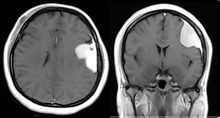

腦膜尾征腦膜瘤附著處的腦膜受腫瘤細胞浸潤,當MRI增強掃描時常有顯著增強,且強化程度超過腫瘤本身的強化程度;在相同部位至少一個掃描層面上出現,並表現為腫瘤鄰近腦膜增粗,遠端變細,稱腦膜尾征(dural tail sign)